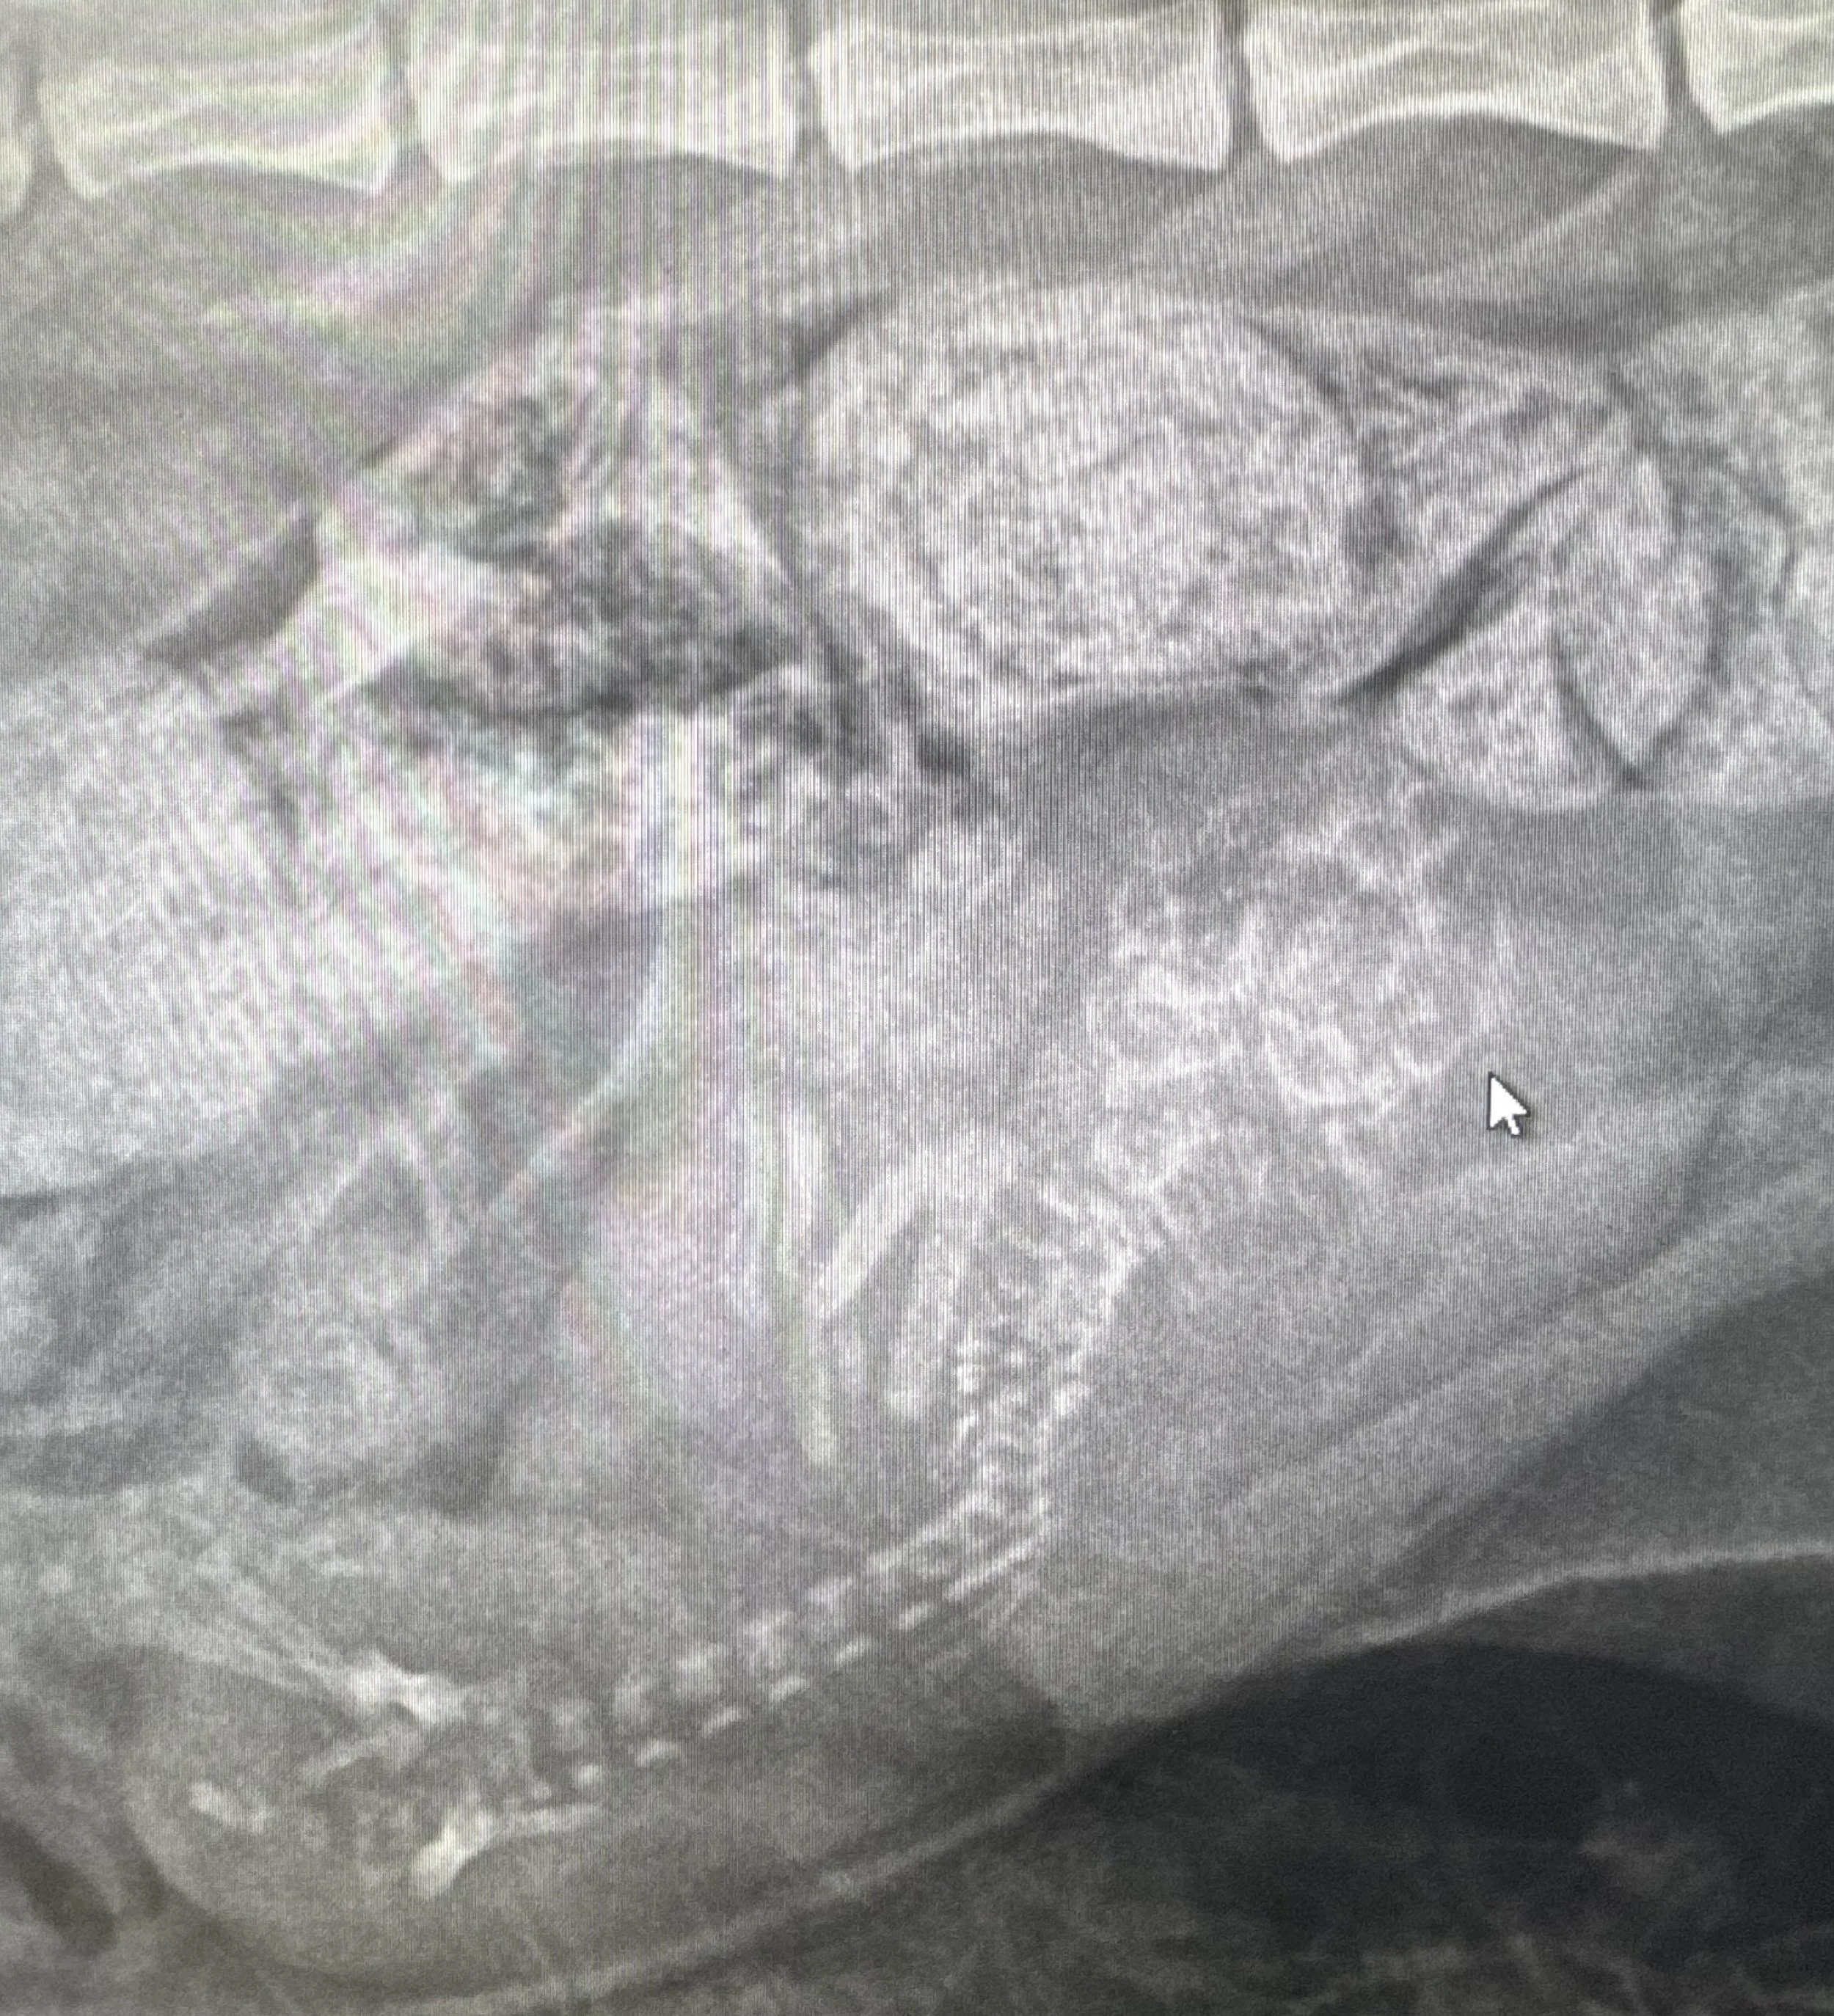

xray canine 50 days to count fetuses

Pregnancy radiographs become especially useful when we are thinking ahead. Once fetal skeletons are visible, the information is not just interesting. It can help support practical planning for the mother’s care.

Strategically, radiographs may help with:

• understanding where pregnancy stands as whelping gets closer

• preparing owners for expected delivery timing

• supporting decision-making if concerns arise late in pregnancy

• giving context for what is happening if labor does not seem to progress normally

• helping us better assess late-pregnancy abdominal findings

The real value is not only in “seeing the puppies.” It is in using imaging information in a way that better supports preparedness, maternal monitoring, and next-step decisions when needed.